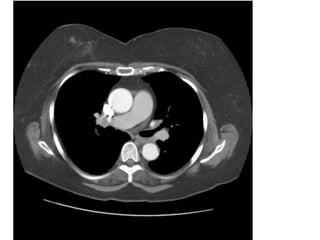

Xeïp thuyø treân phoåi (T) do u phoåi, u phía

trong gaây loài bôø baát thöôøng, ñaäm ñoä u

giaûm so vôùi vuøng phoåi xeïp.

XEÏP PHOÅI THUØY TREÂN